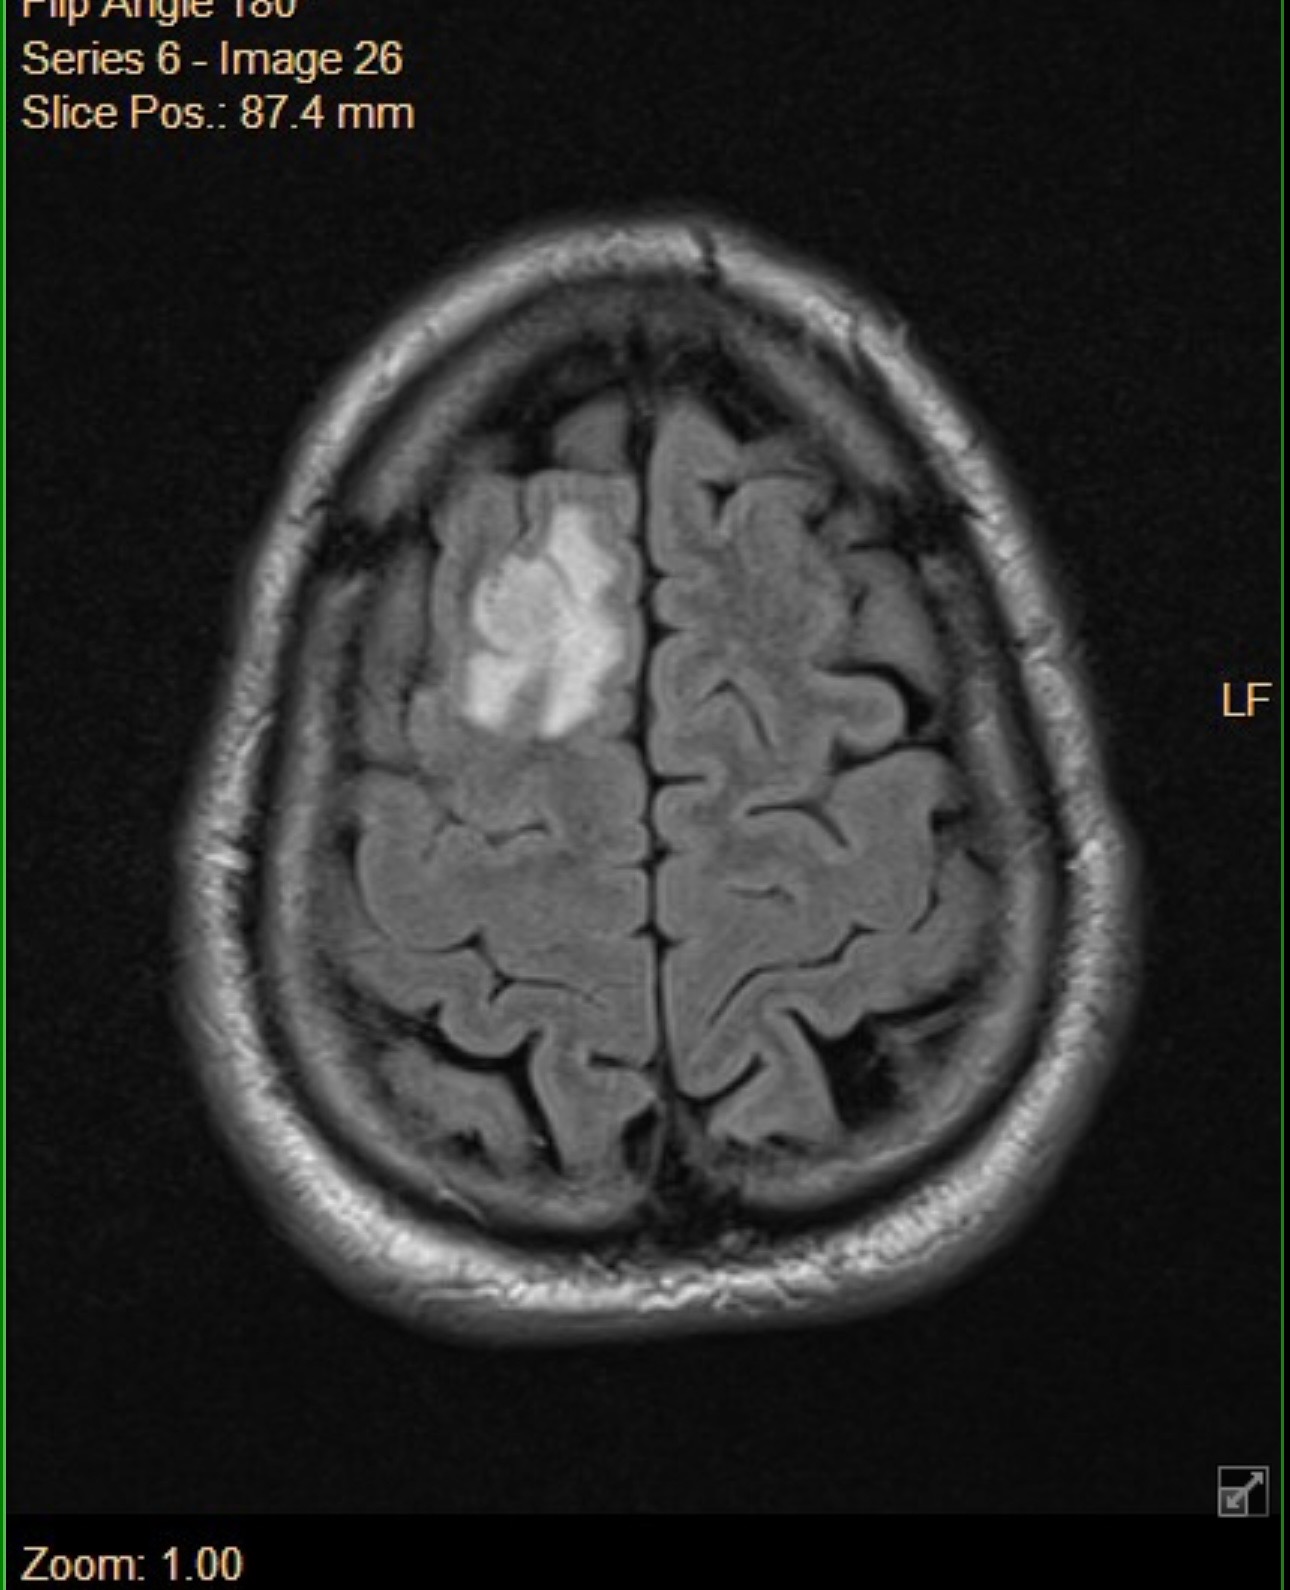

2 years ago, I was diagnosed with Ependymoma Grade 2, a rare type of brain tumor and cancer. Mine is RELA fusion-positive, a particularly aggressive subtype that falls under what’s known as high-grade central nervous system tumors (HCC). Hearing those words from my doctor turned my whole world upside down.